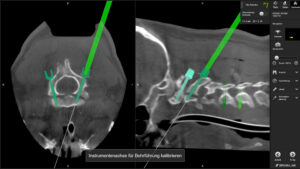

„Auf Höhe der oberen Halswirbelsäule verläuft dieser mit einem sofortigen Atemstillstand und endet meist sofort tödlich“, erklärt der Chefarzt. Prof. Stefan Huber-Wagner und sein Team behandeln schwere und komplexe Verletzungen in der sogenannten Robotic Suite – ein voll ausgestatteter modernster robotischer 3D-Navigations-Hybrid-OP. In

der Robotic Suite können der Patient, seine Wirbelsäule, aber auch die Operationsinstrumente wie Bohrer oder Schrauben während der Operation sehr präzise auf dem Bildschirm angezeigt und gesteuert werden. „Wir können die Schrauben robotisch navigiert setzen und so häufig die zu stabilisierende, beziehungsweise zu versteifende Strecke im Vergleich zum konventionellen Vorgehen verkürzen“, so Prof. Huber-Wagner. Je kürzer diese Strecke ist, umso günstiger ist es für

das funktionelle Ergebnis für den Patienten.